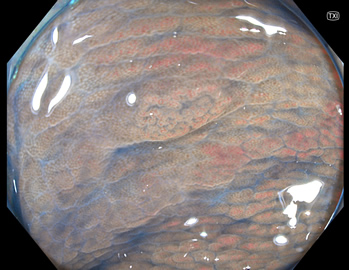

TXIは、「画像の構造を強調する」技術です。これは特別に目新しいものではありません。パソコンの画像編集ソフトや、スマホのアプリでも御馴染みの技術です。しかし、「どのような構造強調が実際に、内視鏡に一番、合うか?(強すぎると不自然になる!)」は、難しい(アナログ的な)課題です。オリンパス社は数タイプのTXIモードを用意しました。半年間の試行錯誤の末、今では下記のモードがベストと判断しました。そして今では「TXI無しの内視鏡は不要(フルタイムTXI)」というまで常用しています。

写真だけ、見ると「言われてみるとTXIの方が認識しやすい。でも僅かの差」と感じるでしょうが、この「僅かの差」が、人間の脳での検出には大きな差になります。青い色素(インジゴ・カルミン)が非常に強調され、粘膜の凸凹が明瞭になるのが特徴です。

通常観察 TXIモード